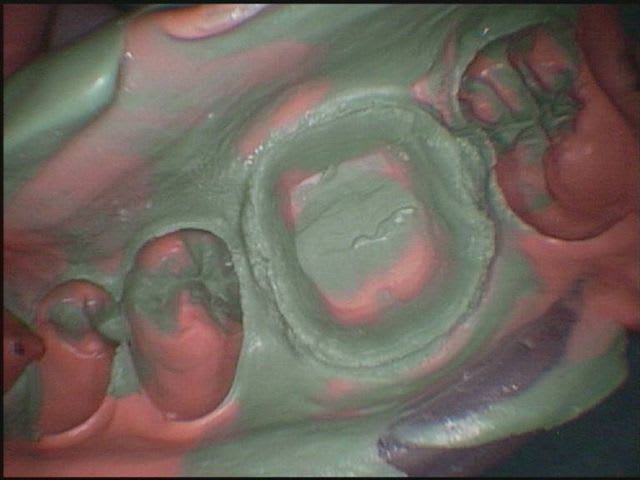

-j'ai fait les empreintes de ces 2 dents, arcades complètes

-j'ai fait les 2 CT, la 16 en auto moulage, la 36 en bloc unifast, la dent naturelle étant trop délabrée pour l'auto moulage, pour ne pas perdre de temps, -j'ai sculpté les CT pendant la prise d'empreinte